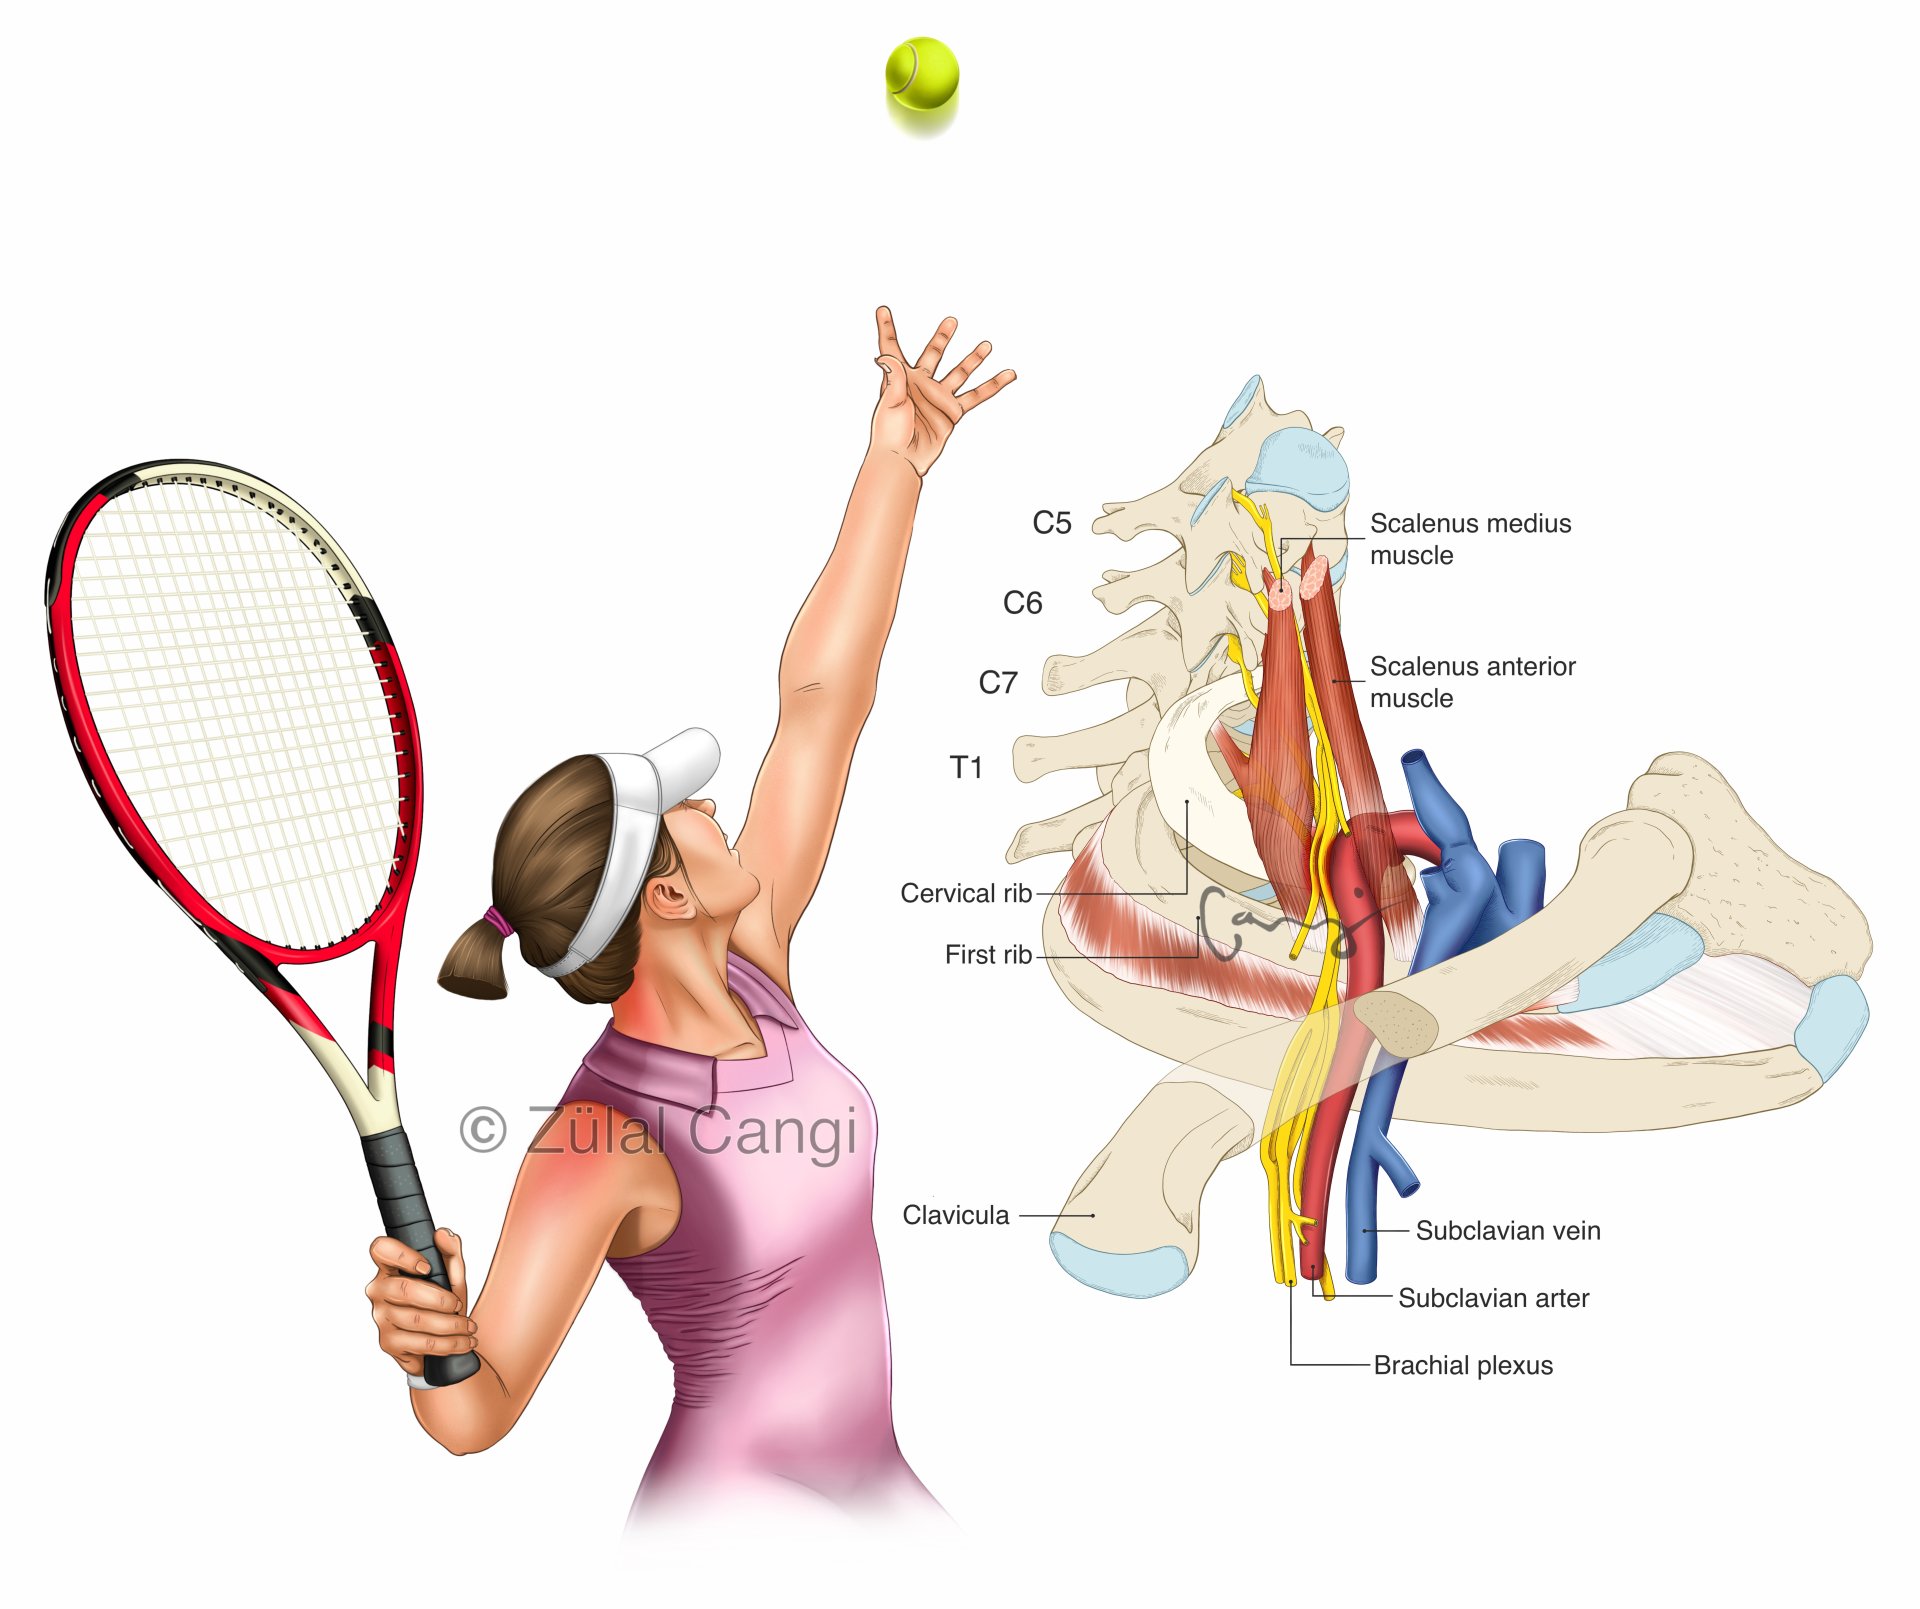

Sanatın estetiğini bilimin kesinliğiyle bir araya getiren Zülal Cangi, medikal ve bilimsel illüstrasyon alanındaki çalışmalarıyla akademik yayınlar, eğitim materyalleri ve çeşitli bilimsel platformlar için görsel içerikler üretmektedir. Amacı, bilimsel bilgiyi yalnızca doğru biçimde aktarmakla kalmayıp, aynı zamanda öğretici ve estetik bir dille görünür kılmaktır.

PORTFÖY